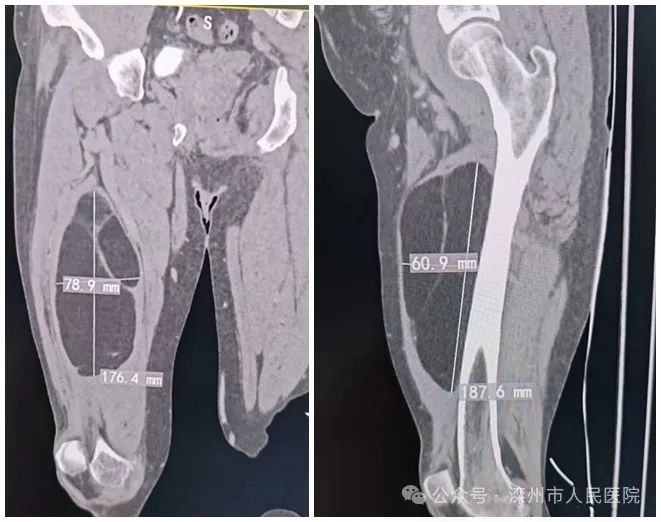

目前,滦州市人民医院脊柱及骨病科成功完成多例“可吸收骨粉配合骨水泥”椎体成形术新技术,为骨质疏松性椎体压缩骨折患者带来更...